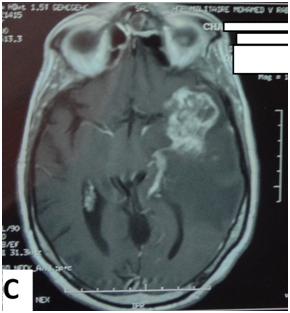

The cerebral MRI showed heterogeneous decreased signal intensity in T1, T2 and Flair-weighted images with variable sizes, surrounded by large area of increased signal intensity in T2 and Flair weighted-images with mass effect on the ipsilateral ventricle (Figure 1). The T1 sequences with intravenous gado injection showed heterogeneous gado enhancement corresponding to the area withT2 and Flair decreased signal intensity (Figure 2). This pattern corresponds to the “swiss cheese” and “soap bubble” aspect. The diffusion weited image showed increased ADC with increased water mobility in left temporal lobe (Figure 3). The radiological conclusion was temporal radionecrosis with large vasogenic edema, or the differential diagnosis of cerebral metastasis of the primary nasopharyngeal carcinoma. Thus, a spectroscopy was performed, and showed decreased peak of N-Acetyl-Aspartate (NAA) and Creatinine (Cr), with normal choline peak. The diagnosis of temporal radio necrosis was established. The patient was proposed to hyperbaric oxygen. His Oto-rhino-laryngeal examination was normal, as much s the chest X-ray. So a daily 45 minutes session, were performed for 10 successive days, associated to bolus of methylprednisolone (240mg/d for 10 days), anti-platelet agent (aspirin 160mg/d). The evolution was favorable, with regression of vestibular signs, improvement of memory and phasic troubles with recovering four lost points in MoCA score. The cerebral CT scan showed partial regression of the gliosis with no more mass effect on the ipsilateral ventricle (Figure 4).

Figure 1 Cerebral MRI in coronal T2-weighted image (A) and axial Flair-weighted image, showing heterogeneous decreasing signal intensity with variable sizes corresponding to necrosis area, surrounded by increased signal intensity corresponding to peri lesional edema with mass effect on the ipsilateral ventricle.

The radiation therapy effectiveness is certain in naso-pharyngeal carcinoma (NPC) and other head and neck malignancies. Knowing the close proximity of inferior and medial temporal lobes to the irradiation field, radiotherapy-related brain damages may occur, especially that the radiation dose is above 65 grays, exceeding the tolerance of the brain tissue. These damages are subdivided to three subtypes related to time of presentation: 1-acute effects (acute encephalopathy during or rapidly after radiation),3 sub acute or early-delayed (somnolence syndrome in up to 12 weeks after radiation)4 and late (months to years after radiation).5 The late effects include radio necrosis, lacunar infarct, parenchyma calcification and white matter changes. Their incidences vary depending on other variables such as concurrent chemotherapy, total dose, fraction dose, time between fraction, the treatment volume, age, arterial hypertension or diabetes and TNM tumor status.6 Radio necrosis incidence is above 5% when the total dose did not exceed 60 grays, and the fraction daily size less than 2 grays.7 The first case of cerebral radio necrosis in extra cranial malignancy was described by Fischer and Holfelder in 1930.8 Nowadays, hundreds cases were reported over the world, where the most common site of malignancy is the nasopharynx followed by the scalp and the sinonasal tract.9 In 80% of cases, the diagnosis of cerebral radionecrosis is established within the 3 years after the last dose of radiotherapy.10 In our patient, this period was 6 years. Three hypotheses sustain radio necrosis mechanism: on one hand the vascular hypothesis suggest endothelial cell damages with extracellular edema and cytokine release leading to demyelination and necrosis. On the other hand the, the glial hypothesis suggests a high sensibility of glial and oligodendrocytes cells to radiation, leading to their direct damages with parenchyma atrophy. The third recent mechanism suggests a host’s immune response with mediation by pro-inflammatory cytokines.11,12 Cerebral radio necrosis symptoms are wide variable and latent. The most common are consciousness changes, seizures, vertigo, dizziness, irritability or memory impairment. In front of such neurological or psychiatric signs, encephalopathy must be ruled out before considering cerebral radio necrosis.10 Patients with temporal radio necrosis have more significant change in their cognitive function, reflected in short-time memory, language, attention, delayed recall, orientation, and executive function. MMSE and MoCA are widely known to evaluate general cognitive function.13 As in brain tumor patients, MoCA has been documented for having more sensitivity in objectifying the decline. This was due to its large screening demanding more assessment of memory, information speed treatment, executive function, attention, new learning and visuo-spatial function.14 In our case, the MMSE was normal, time that MoCA showed cognitive impairment while exploring memory, naming and attention. Thus, we recommended using MoCA as a standard cognitive scale to detect impairment in patients treated with radiotherapy for head and neck cancer. Moreover, temporal radio necrosis causes neuropsychiatric troubles, dominated by irritability, anxiety and depression. Our patient showed no abnormality, using the Hamilton depression scale (HAMD), and Hamilton anxiety scale (HAMA). The real challenge is to distinguish cerebral radio necrosis (CRN) from cerebral metastatic or recurrent tumor (CTM). For this aim, magnetic resonance image with apparent diffusion coefficient (ADC), perfusion imaging and spectroscopy studies showed enough arguments to avoid recourse to surgery with extensive pathological evaluation.15 Typical MRI aspect in gado T1-weighted image is called “Swiss cheese” or “soap bubble”. These two patterns refer to heterogeneous non-enhancing zones inside the area of contrast enhancement (soap bubble), associated to various sizes of necrotic scattered areas (swiss cheese). The second pattern is the increased water mobility in radiation necrosis leading to increase ADC, which did not exist in metastatic or recurrent brain tumor.16\ For spectroscopy, decreased creatinine (Cr) and N acetyl aspartate (NAA) peak are more suggestive of cerebral radionecrosis rather than cerebral tumor where choline (Cho) peak increased. Thus, the Cho/Cr and Cho/NAA are good landmarks to distinguish cerebral radio necrosis from tumor.17 The last argument is the hypoperfusion in CRN, contrasting with hyperperfusion in CTM. The use of PET with 18-FDG or amino-acids is still controversial. Our case illustrates the swiss cheese and soap bubble pattern, concordant with decreased NAA and Cr peak. Concerning therapies, corticosteroid (intravenous relayed by oral therapy) showed enough effectiveness in CRN. This therapy reverses the breakdown of blood-brain barrier with anti-inflammatory and anti-edema action.18,19 Hyperbaric oxygen, anti-platelets and anticoagulant have been used to repair microcirculation and regional blood supply caused by radio necrosis.20,21 An over expressing of Vascular Endothelial Growth Factor (VEGF) was remarked in radio necrosis, and was targeted by humanized murine monoclonal antibody named Bevacizumab. It appears to be a promoting agent against CRN. Nevertheless, the optimal scheduling and treatment duration have not been yet established.22 The recourse to surgery in CRN should be leaded carefully and strictly, and medical treatment should be more used in its stead.